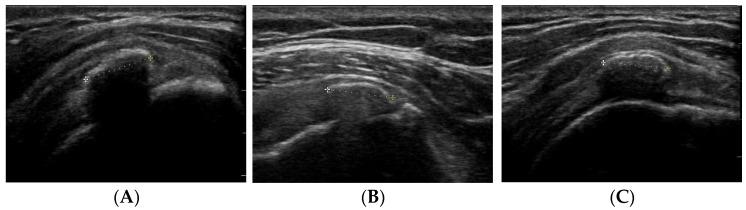

: Shoulder pain is a very common health issue among adults, being 8% due to calcifying tendinopathies (CT) of the shoulder. The evolutionary process of this lesion can be classified according to Bianchi Martinoli, depending on the ultrasound appearance. In 50% of cases, with first-line treatments, they resolve spontaneously. However, in the remaining 50%, they become chronic, requiring other lines of treatment, such as shock waves (ESWT) or ultrasound-guided barbotage (US-PICT). : The objective focuses on comparing the improvement in pain using the visual analgesic scale (VAS) and shoulder joint balance (ROM) in patients with CT based on the treatment received, stratifying according to the characteristics of the injury, with the aim of protocolizing said treatment. : Randomized analytical controlled clinical trial in blocks with two arms according to the Bianchi Martinolli classification (I or II/III) in 56 patients affected by chronic pain by CT. The decision to treat will be made randomly 1:1, based on the treatment assigned to the previous patient. Results will be evaluated in three moments (1, 3, and 6 months). The following variables will be collected: VAS, Lattinen test, ROM (flexion, abduction, external and internal rotation), patient global improvement impression scale (PGI-I), global improvement impression scale (CGI-C). : The use of ESWT or US-PICT as treatments is a widely used practice in the daily life of this pathology. However, despite knowing that both treatments are useful in chronic CT, there are no known data or protocols by which one therapy is chosen over another, much less the influence that the evolutionary stage can have of the injury in the results obtained.

肩部疼痛是成年人中非常常见的健康问题,其中8%是由肩部钙化性肌腱病(CT)引起的。根据比安奇·马蒂诺利的分类,这种病变的演变过程可根据超声表现进行分类。在50%的病例中,通过一线治疗,病情会自发缓解。然而,在其余50%的病例中,病情会转为慢性,需要其他治疗方法,如冲击波(ESWT)或超声引导下注射(US-PICT)。:目的是根据所接受的治疗,比较使用视觉镇痛量表(VAS)和肩关节平衡(ROM)来评估CT患者疼痛改善情况,并根据损伤特征进行分层,以便将该治疗方案化。:对56例受CT慢性疼痛影响的患者,根据比安奇·马蒂诺利分类(I或II/III)进行双臂随机分析对照临床试验。治疗决策将基于前一位患者所分配的治疗方案,以1:1的比例随机进行。结果将在三个时间点(1、3和6个月)进行评估。将收集以下变量:VAS、拉蒂宁试验、ROM(屈曲、外展、外旋和内旋)、患者总体改善印象量表(PGI-I)、总体改善印象量表(CGI-C)。:在这种疾病的日常治疗中,使用ESWT或US-PICT作为治疗方法是一种广泛应用的做法。然而,尽管知道这两种治疗方法对慢性CT都有用,但尚无已知数据或方案可据此选择一种治疗方法而非另一种,更不用说损伤的演变阶段对所获结果可能产生的影响了。